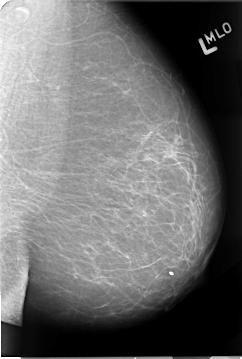

B_3067_1.LEFT_MLO

LEFT_MLO LINES 4656 PIXELS_PER_LINE 3136 BITS_PER_PIXEL 12 RESOLUTION 50 NON_OVERLAY